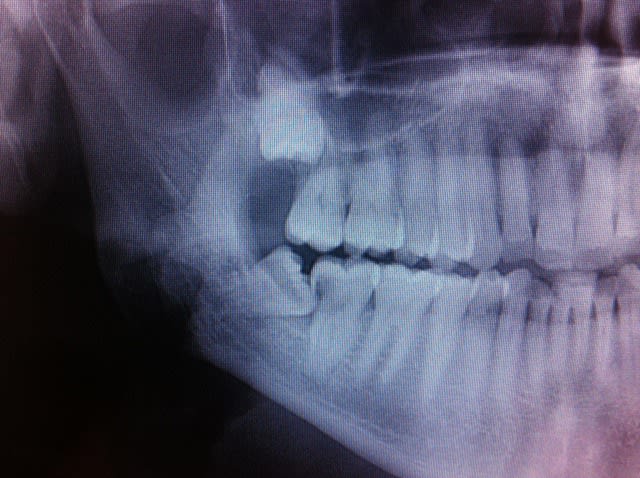

Voici le scanner d'un patient chez qui l'extraction des dents 47 et 48 est indiquée. Etant donné le positionnement de ces dents par rapport au nerf, j'aurais aimé avoir vos différents points de vue quant à la meilleure solution thérapeutique à adopter.

J ai du mal avec le scanner. Retro alveolaire, pano pour vue d ensemble?

Il y a un risque de compression legere du V3 sans plus. Bien separer les racines de 48 et voir avec 47, si elle sort facilement sinon separer aussi apres lambeau 47-48 et fraisage osseux vestibulaire pour facilier une extraction dans sens linguo vestibulaire.

Age du patient? Bien informer du risque de compression du V3 avec perte transitoire de sensibilite au niveau mentonnier (2-3 mois).